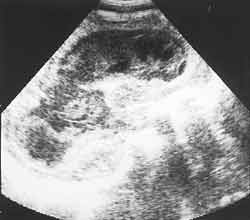

Ультразвуковая диагностика гнойных менингитов у детей первого года жизни.

Рис. 3. Клебсиелезный менингит. (Слева) Некротические массы ткани мозга в острый период. (Справа) Стадия формирования гидроцефалии.